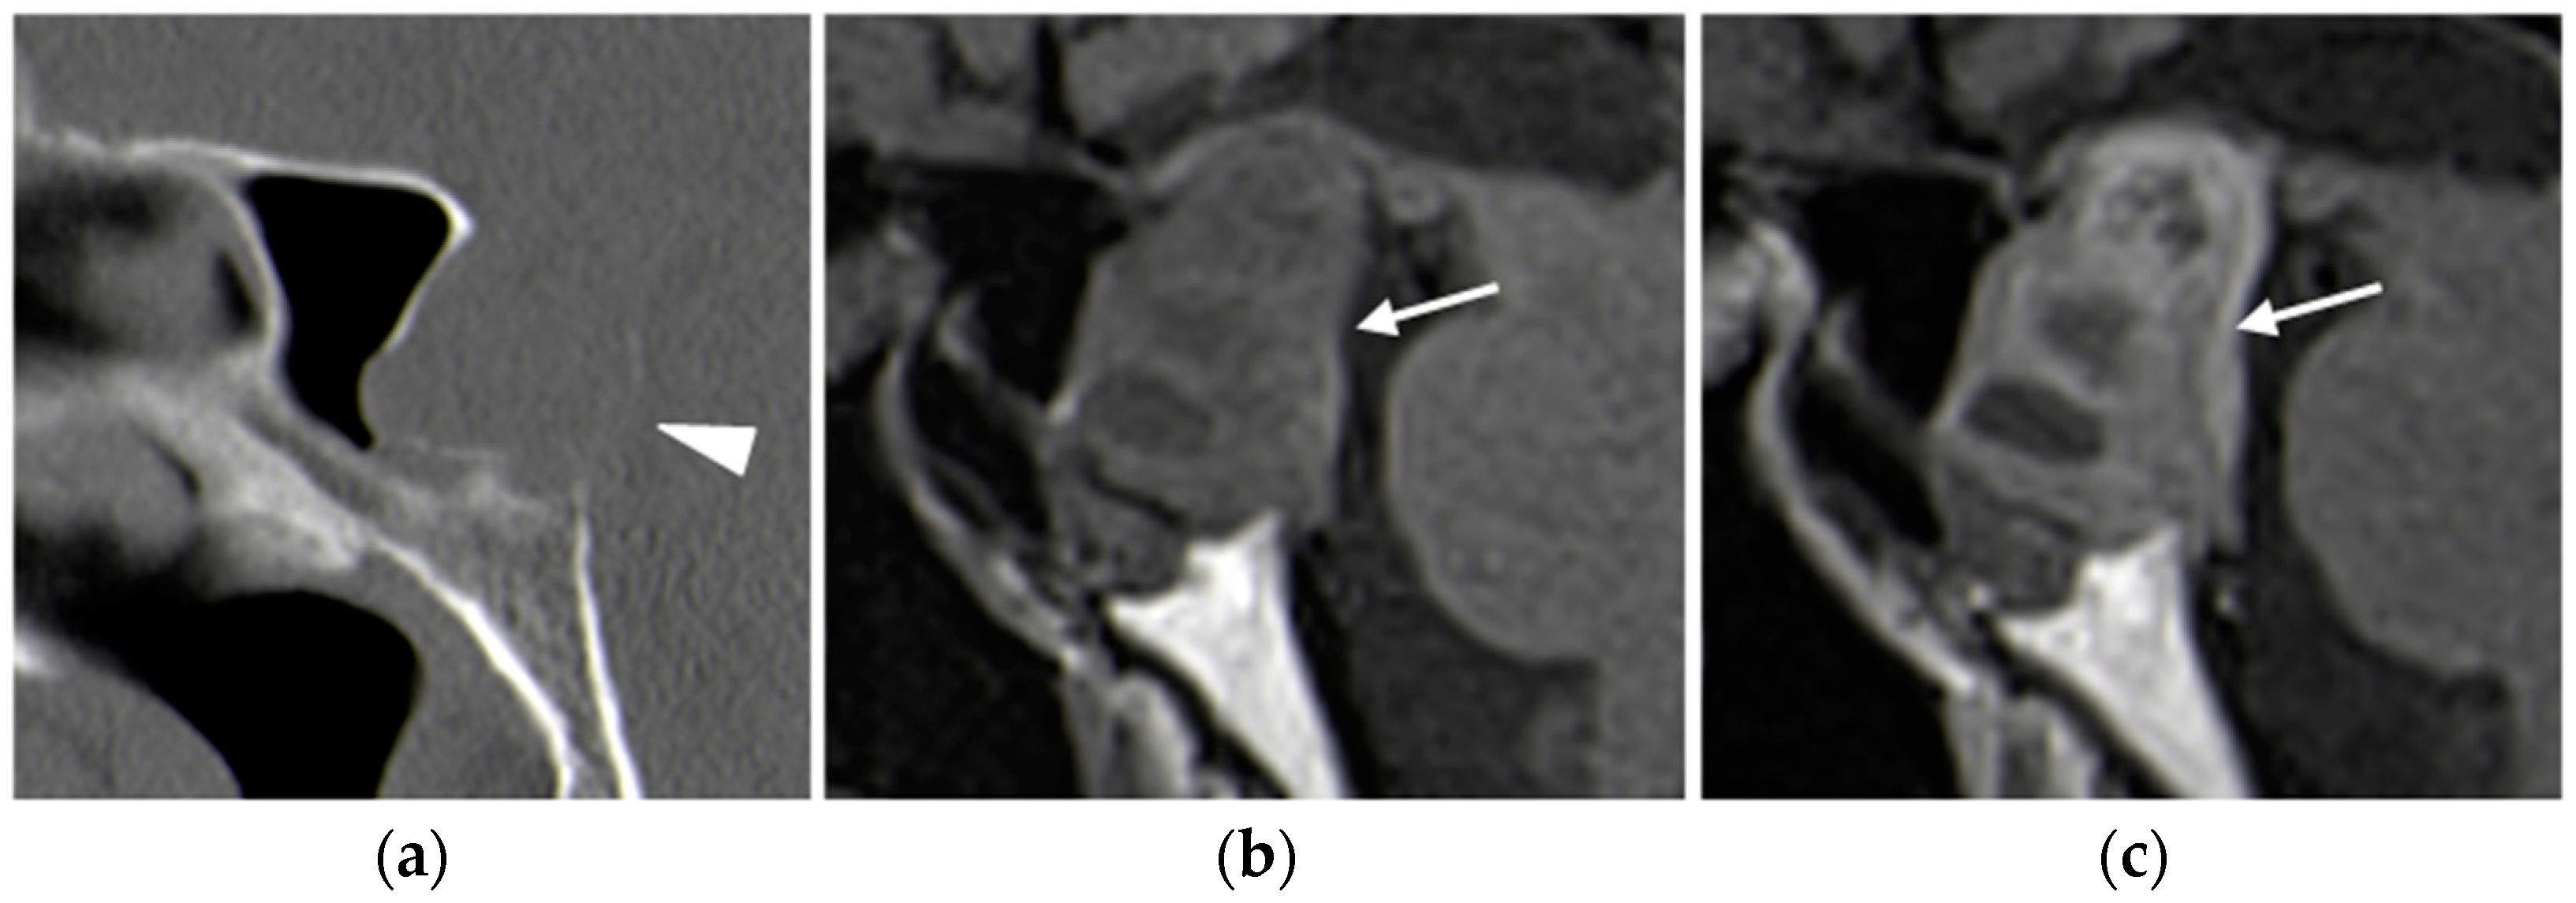

Pituitary macroadenomas can have a heterogeneous signal on unenhanced sequences due to solid, cystic, necrotic, and hemorrhagic areas. After contrast administration, macroadenomas typically show heterogeneous enhancement (Figure 9).

Figure 9.

Pituitary macro-adenoma. Sagittal plane basal CT (a) image shows a large mass causing bone remodeling of the sella turcica and thinning on the posterior wall of the sphenoid sinus (arrowhead). MRI T1-weighted images before (b) and after (c) contrast administration confirm the presence of a large hypointense lesion (arrows) arising from the pituitary gland, with heterogeneous enhancement.